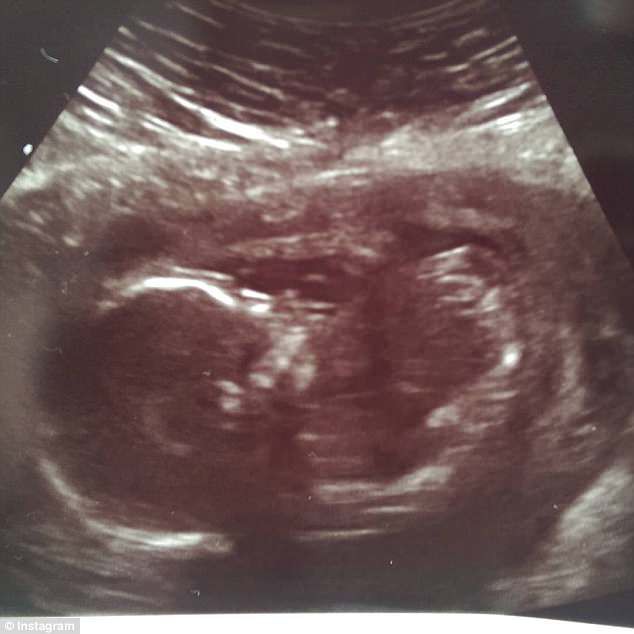

英國27歲媽媽Cally Hibbert在懷孕18週時穿羊水,醫生告訴她BB只有10%的倖存機會,她得知後不斷搜尋方法,望能救活腹中兒子。於是,她決定用「喝水補羊水」方法來拯救他兒子的生命。最後,囝囝Leo終順利出生,重一磅十安士,產後留院觀察3個月。

Cally:「所有媽媽都認為我的孩子是奇蹟。」最後,在28週時,宮縮開始了,Cally最終生了重一磅十安士的兒子Leo,留院觀察3個月至6磅一安士時,終可以帶回家,現今兒子已經兩歲了。